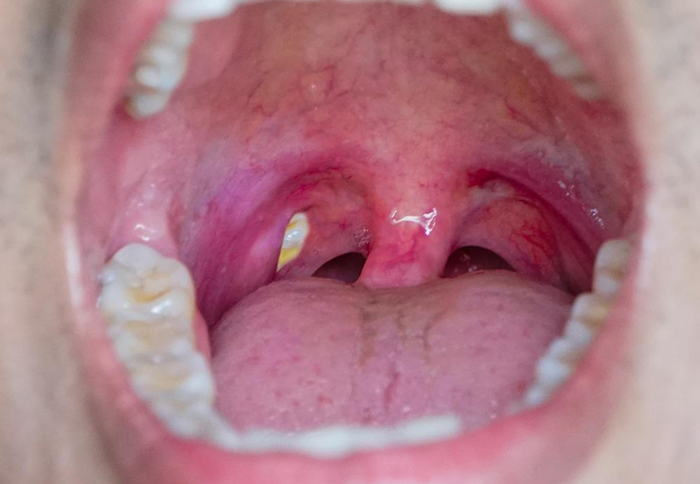

متاسفانه مواردی مثل سنگ لوزه (Tonsillolith)، آبسه دورلوزه (Peritonsillar abscess) و تومورهای خوشخیم/بدخیم، را کیست معرفی میکنند درحالی که این چنین نیست و توده یا بافت هستند.

کیستهای لوزه در بیشتر موارد بیخطر و غیرسرطانی هستند و بسیاری از افراد بدون اینکه متوجه شوند، سالها با این کیستهای کوچک زندگی میکنند. با این حال، زمانی که این کیستها رشد کنند یا دچار عفونت شوند، میتوانند مشکلاتی مانند احساس گیرکردن چیزی در گلو، ناراحتی هنگام بلع، تنفس دشوار یا حتی بوی نامطبوع دهان به وجود بیاورند. تشخیص دقیق این کیستها اهمیت بسیار زیادی دارد، زیرا گاهی با آبسه یا سنگ لوزه اشتباه گرفته میشوند. درواقع تودهٔ سفید/زرد روی لوزه اغلب سنگ لوزه یا ترشحات تونسیلیت است و آبسهٔ دورلوزه هم تودهمانند دیده میشود؛ اینها کیست نیستند و درمان متفاوتی دارند.

معمولاً کیستهای لوزه به صورت تودههای بدون درد ظاهر شده و بسیاری از بیماران تنها هنگام معاینه پزشکی متوجه آن میشوند، هرچند برخی ممکن است احساس جسم خارجی در گلو یا مشکل در بلع را تجربه کنند. در موارد نادر، این کیستها با سرفه خشک، گوش درد یا گلودرد خفیف همراه هستند. در مقابل، سرطان لوزه اغلب با علائم هشداردهندهای مانند عدم تقارن اندازه لوزهها (یک لوزه بزرگتر از دیگری)، توده بدون درد در گردن، گلودرد مداوم، گوشدرد یکطرفه، اشکال در بلع، بوی بد دهان، احساس دائمی جسم خارجی در گلو، خونریزی از لوزه یا تورم غدد لنفاوی همراه است. لازم به ذکر است که یک تودهٔ بدوندرد در گردن از علائم شایع سرطان لوزه است و نیاز به ارزیابی فوری دارد.

درنهایت این تفاوتهای کلیدی به پزشکان کمک میکند تا تشخیص دقیقتری داشته باشند، زیرا سرطان لوزه نیاز به اقدامات فوری مانند بیوپسی و تصویربرداری دارد. در مقابل کیستهای خوشخیم تنها در صورت ایجاد ناراحتی نیاز به درمان دارند.